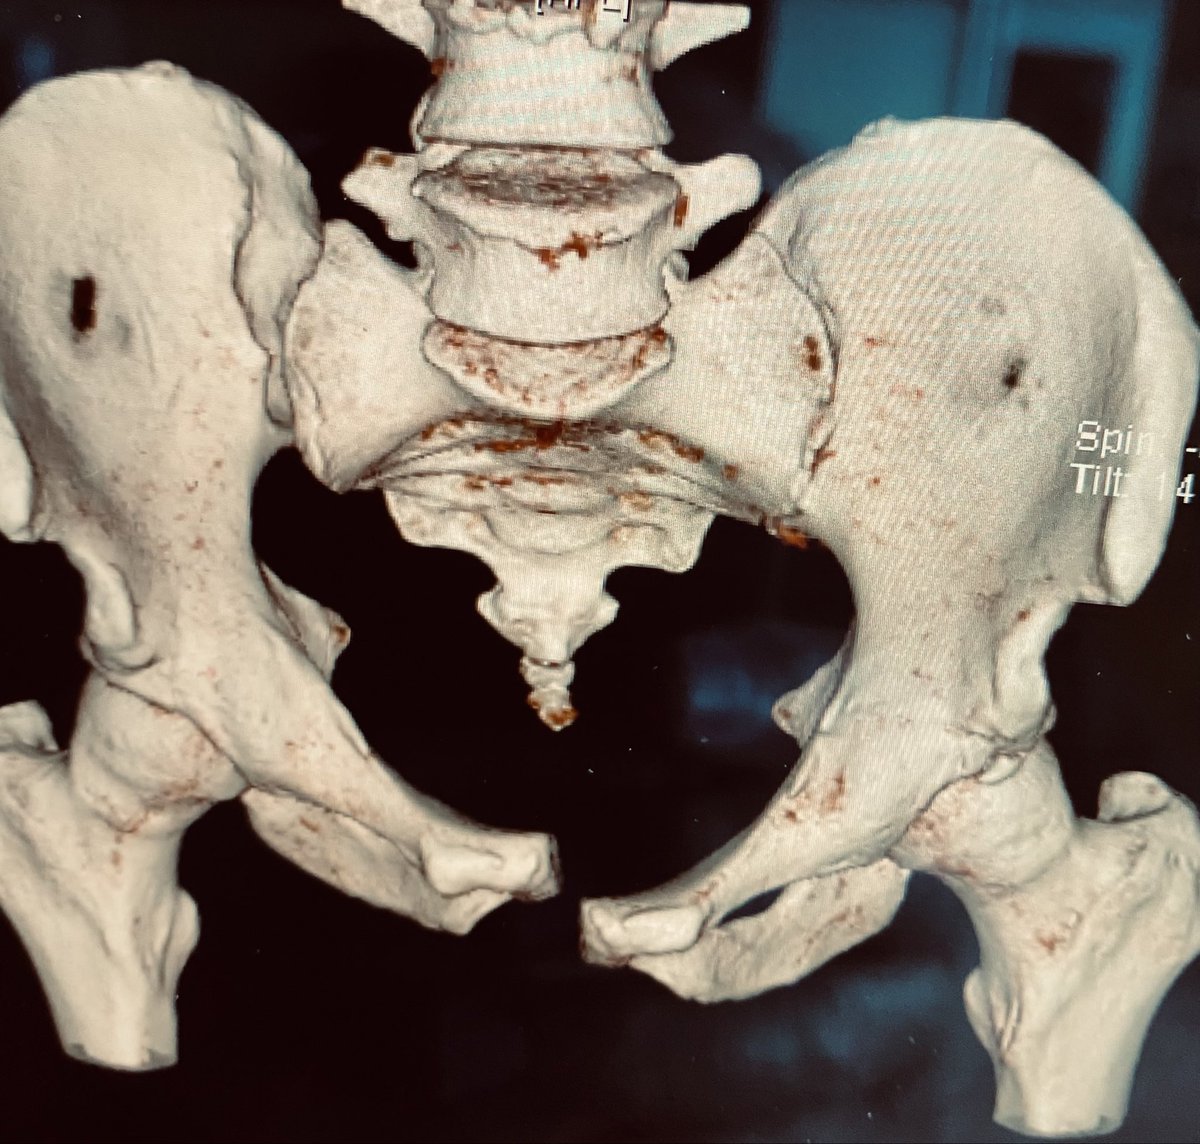

This surface rendered pelvic inlet image demonstrates the right hemipelvic displacement and deformity